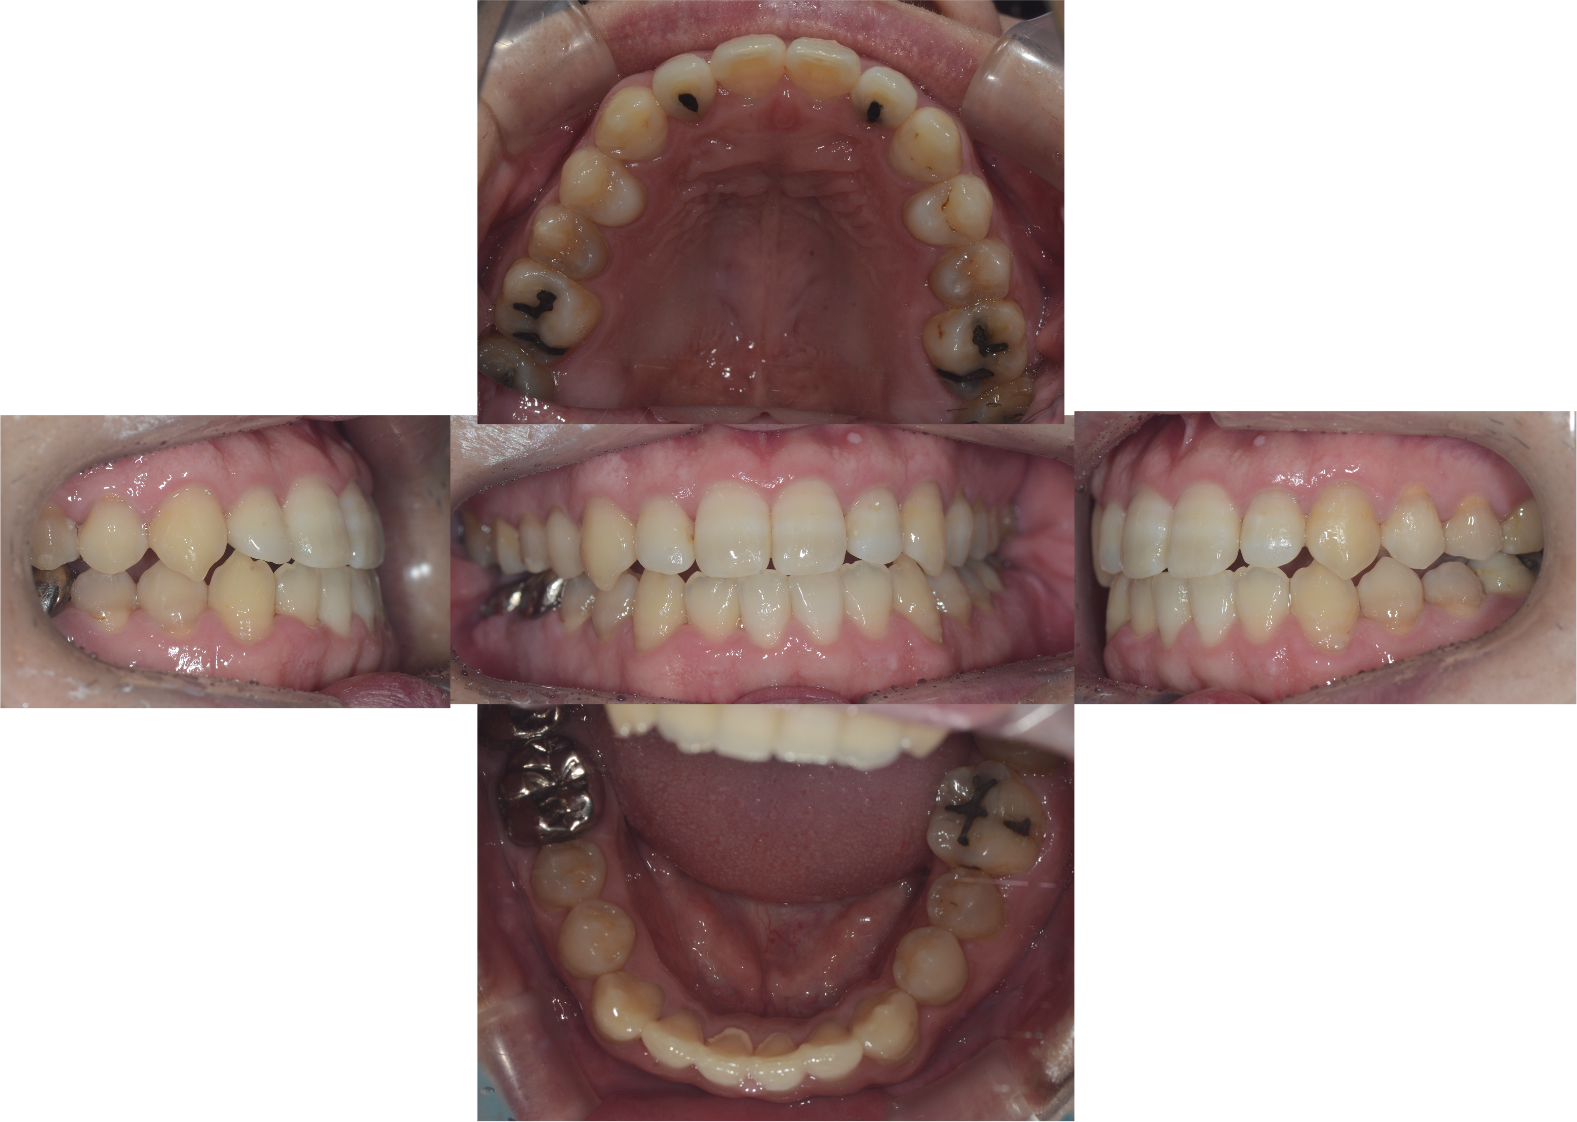

主訴 | 歯がガタガタしている。左奥歯が噛んでいない。 |

---|---|

治療名 | ワイヤーによる矯正治療(非抜歯症例) |

治療期間 | 20ヶ月(1年8ヶ月) |

治療費用 | 75万円程度 |

来院頻度 | 1ヶ月に1回程度 |

Before・after